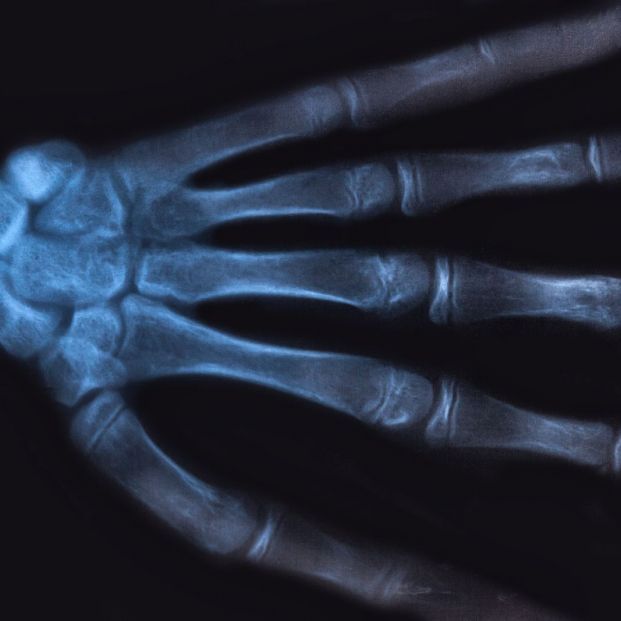

Un estudio publicado en la revista Scientific Reports muestra evidencias de que la oxitocina, producida por el hipotálamo y a veces conocida como la hormona del amor, puede ser un fuerte aliado en la prevención de la osteoporosis, según un estudio realizado por científicos de la Universidad del Estado de São Paulo (Brasil). En concreto, el trabajo ha evidenciado que esta hormona, cuando se administró a ratas hembras al final de su período fértil, revirtió los signos precursores de la osteoporosis, como la reducción de la densidad ósea, la disminución de la fuerza de los huesos y la falta de sustancias que promueven la formación de huesos.

Las ratas estudiadas estaban en "periestropausia", considerada como el equivalente de la perimenopausia en los seres humanos, que estaban sometidas a un proceso natural de envejecimiento. Treinta y cinco días después de administrar la oxitocina, los investigadores analizaron muestras de sangre y de tejido del cuello del fémur (la parte superior del fémur justo debajo de la articulación de la cadera y el lugar más común para una fractura de cadera), comparando los resultados con los de diez ratas hembra de 18 meses de edad a las que no se les administró la hormona. No hubo pruebas de osteopenia (pérdida de densidad ósea) en los animales tratados con oxitocina, en contraste con el grupo de control.

Según los investigadores, los resultados vienen a demostrar que la oxitocina ayuda a modular el ciclo de remodelación ósea en ratas senescentes. Los animales que recibieron la hormona mostraron un aumento en los marcadores bioquímicos asociados con la renovación ósea y en la expresión de proteínas que apoyan la formación y mineralización del hueso", apunta Dornelles. El análisis de las muestras de sangre mostró un aumento de la actividad de los principales marcadores de formación ósea, como la fosfatasa alcalina.

"Esta sustancia es producida por células osteogénicas y está asociada a la mineralización. También observamos una actividad reducida de la fosfatasa ácida resistente al tartrato, un marcador de la resorción ósea", señala la científica. Las ratas tratadas con oxitocina tenían huesos más densos.